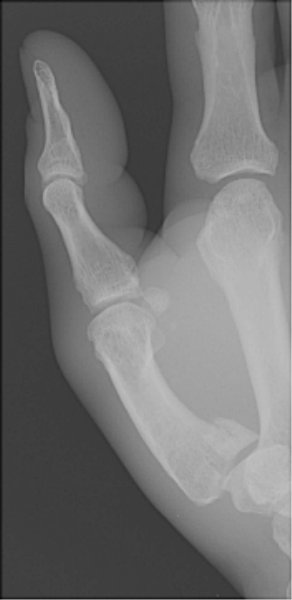

Return to Bennett Fracture